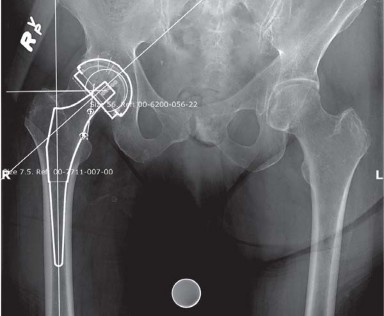

INDICATIONS Total hip replacement (THR) in the setting of developmental dysplasia of the hip (DDH) is indicat…